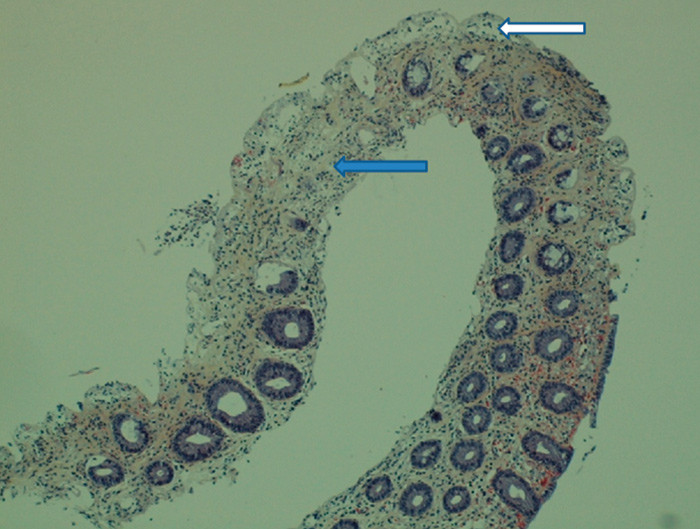

Opplysningen om friskt blod i avføringen førte til at man valgte å gjøre CT colon på mistanke om kolitt. CT colon viste en uspesifikk veggfortykkelse i venstre del av colon. Røntgen av tynntarm påviste verken kalibervekslinger, fortykket vegg eller stenoser. Ved koloskopi fant man forandringer med flekkvis rubor, ødem og submukosale blødninger i colon sigmoideum og colon descendens opp til venstre fleksur (fig 1). Histologi av tykktarmslimhinnen viste løsnet overflateepitel, fravær av krypter i tillegg til atrofi og ødem (fig 2).

Det histologiske funnet passet ikke med inflammatorisk tarmsykdom, men var typisk for iskemisk kolitt. Samlet passet dette best med iskemisk skade av tarmen.